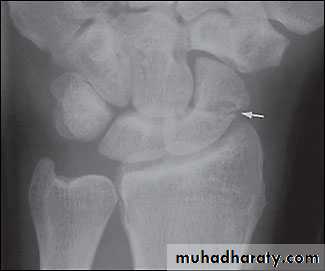

Scaphoid fractures:Its account for almost 75% of all carpal fractures, its rare in the elderly and children.

Mechanism of fracture: fall on dorsiflexed hand.

X-ray : AP, Lateral and oblique views.